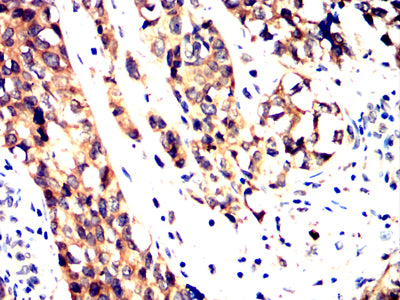

Immunohistochemical analysis of paraffin-embedded human bladder cancer tissues using PPID mouse mAb with DAB staining.